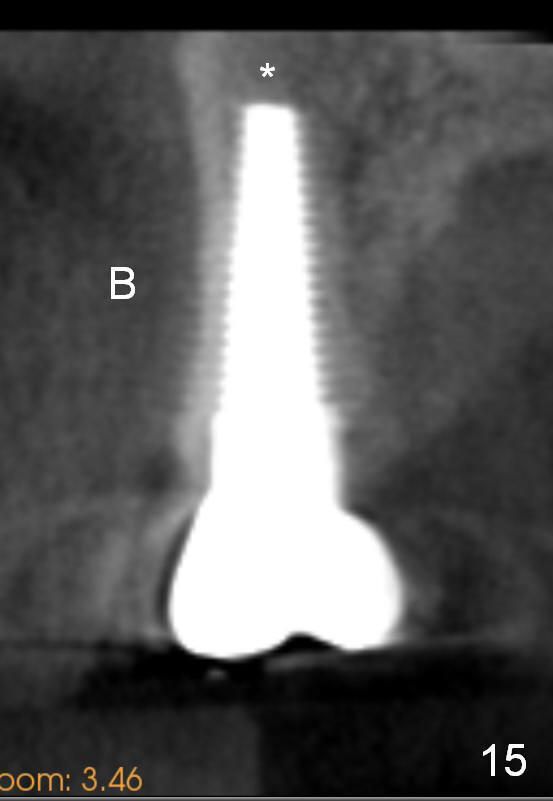

Eight months post cementation, CBCT shows periapical infection of the neighboring teeth (Fig.14 *).  There is still apical bone for a longer implant (Fig.14 green line, Fig.15 *).  The implant functions 1.5 years post cementation. When the implant at the lower bicuspid fails, the patient reveals that he is a diabetic.  The latter is the main reason of delayed healing.